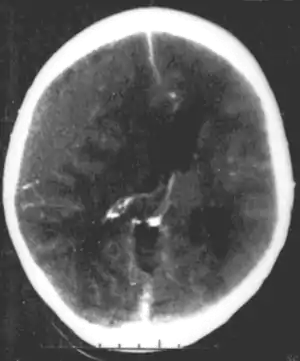

A number of infectious diseases can be transmitted congenitally (either before or at birth), and can cause serious neurodevelopmental problems, as for example the viruses HSV, CMV, rubella (congenital rubella syndrome), Zika virus, or bacteria like Treponema pallidum in congenital syphilis, which may progress to neurosyphilis if it remains untreated. Protozoa like Plasmodium[22] or Toxoplasma which can cause congenital toxoplasmosis with multiple cysts in the brain and other organs, leading to a variety of neurological deficits.